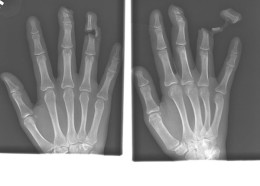

Чудни ренгенски снимки